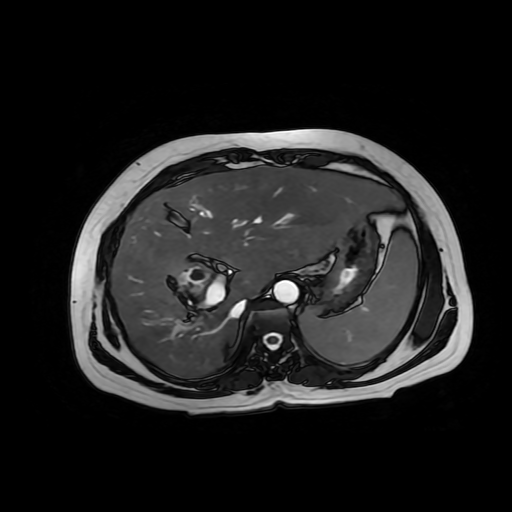

HISTORIA DEL PACIENTE

Paciente de sexo femenino, de 56 años de edad, refiere dolor en cuadrante superior derecho, indica que le realizaron colecistectomía de hace mas o menos 7 años, presenta cuadro de ictericia de 6 meses de evolución. Médico tratante le solicita estudio de Resonancia de vías biliares (Coilangioresonancia)

Se prepara a paciente previo a ingreso a zona 4 del área de resonancia magnética, paciente se presenta con catéter en región anterior del antebrazo, se utiliza bobina de abdomen de 16 canales y se procede a obtener localizadores en los tres planos, para luego adquirir imágenes en diferentes planos, en secuencias espin echo, eco de gradiente, secuencia de difusión. Se utiliza medio de contraste hepatoespecifico con dosis sugerida por fabricante.

HALLAZGOS IMAGENOLOGICOS

Se observa dilatación de las vías intra hepáticas a expensas de sus ramas hepáticas derecha, anterior y posterior, hepática izquierda y hepática común. El hepático común da la apariencia de estar anastomosado a un asa de intestino, lo que sugiere la posibilidad de una cirugía entero biliar.

No se logra observar el colédoco.

1. Dilatación de vías biliares intrahepáticas

2. Anastomosis entero biliar

3. Colangitis aguda